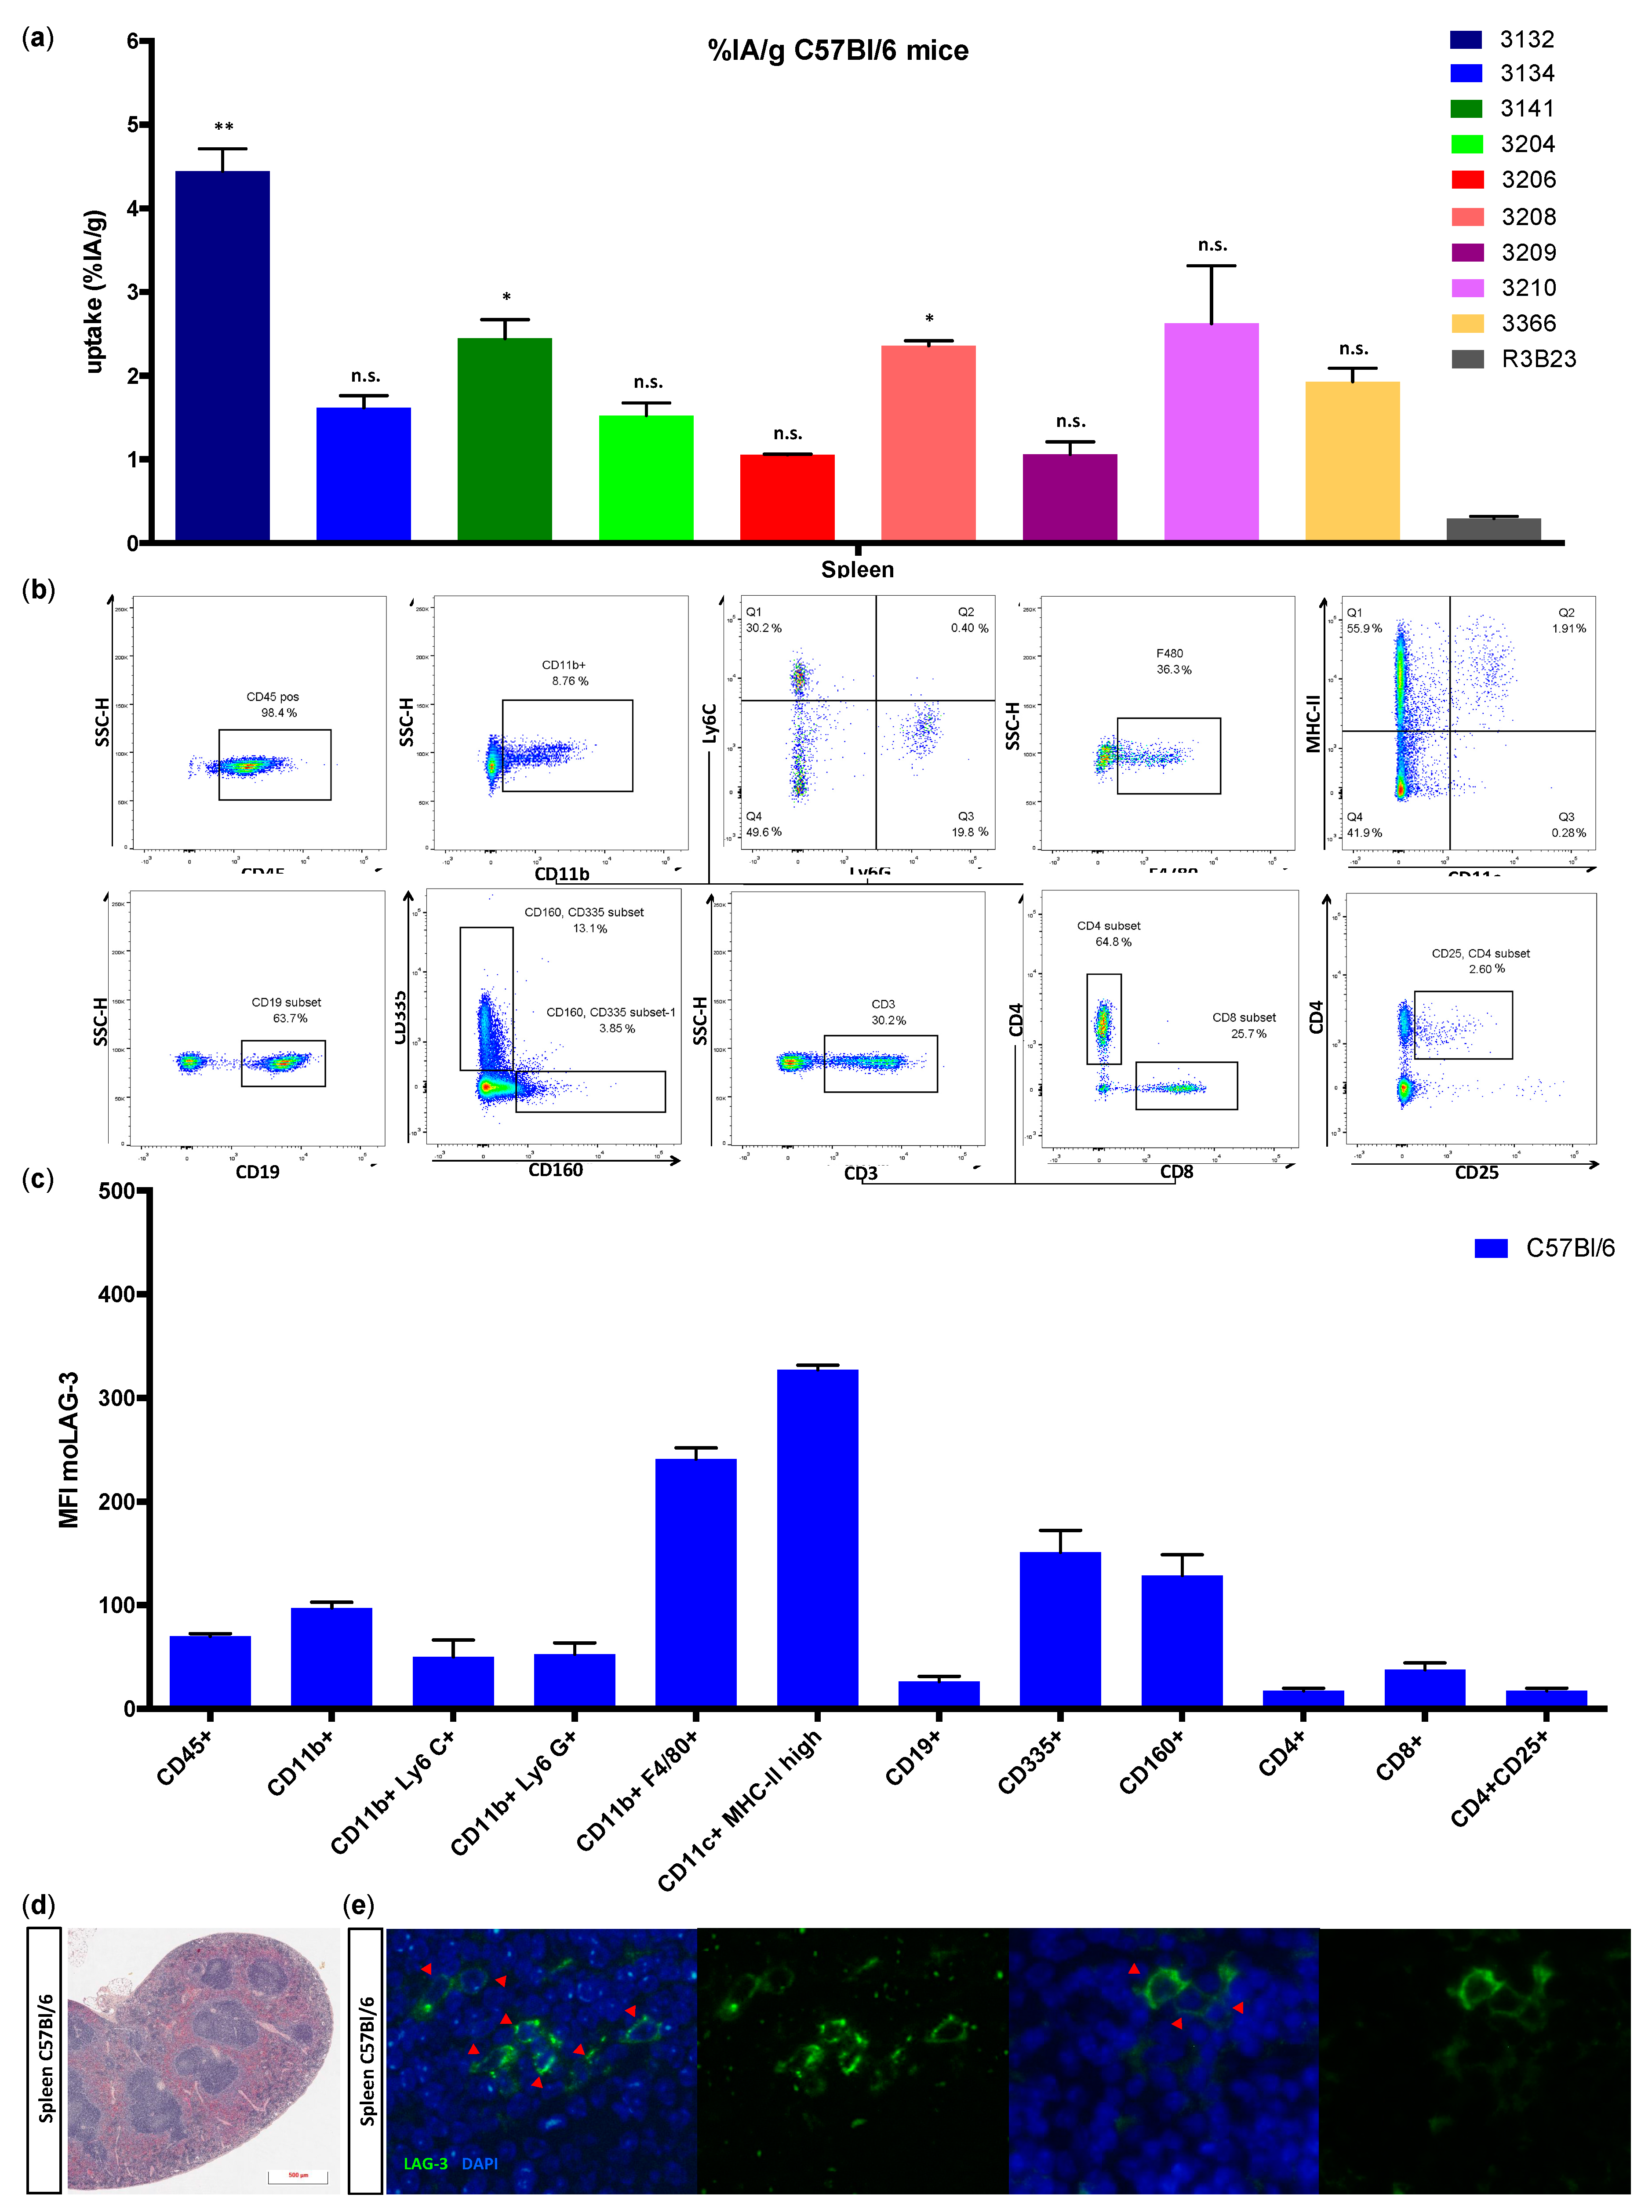

We showed that lymphocytes, residing in the lymph nodes of naive and healthy C57BL/6 mice, express low levels of moLAG-3. In contrast, lymph node residing antigen presenting cells expressed higher levels of moLAG-3. Within the spleen, the immune cell population (CD45

+) with the highest moLAG-3 expression could be detected on antigen-presenting cells, like dendritic cells and macrophages, and on NK and NKT cells [

4]. Moreover, very low amounts of moLAG-3 are expressed on CD19

+ B cells, and CD4

+ and CD8

+ T cells, which is comparable to the low levels found on lymphocytes isolated from lymph nodes. Nevertheless, out of nine different

99mTc-labeled anti-moLAG-3 Nbs, Nb 3132 was still able to detect and visualize low levels of moLAG-3 expressing immune cells residing in the spleen and lymph nodes. Although the affinity of Nb 3132 for moLAG-3 is rather low, injection of

99mTc-labeled Nb 3206, with a 10-fold higher affinity for moLAG-3, was less able to detect and image moLAG-3 expressing cells in the spleen and lymph nodes. Interestingly, when evaluating our Nbs for binding on moLAG-3 expressing cells using flow cytometry, Nb 3132 showed the highest binding of all Nbs. This observation could mean that recombinant moLAG-3 coated chips for SPR or membrane expressed LAG-3 for flow cytometry analysis are not completely identical and thus could lead to under or overestimation of Nb affinity. Moreover, the affinity of Nbs is only one of the parameters used to predict its potential for imaging purposes. Vaneycken et al. showed that the dissociation rate of Nbs did not correlate with tumor uptake since their Nb with the slowest dissociation rate targeted poorly to tumors, while another Nb, with a fast dissociation rate, targeted very well [